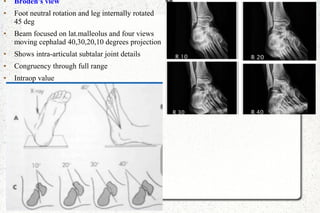

● Broden's view

● Foot neutral rotation and leg internally rotated

45 deg

● Beam focused on lat.malleolus and four views

moving cephalad 40,30,20,10 degrees projection

● Shows intra-articulat subtalar joint details

● Congruency through full range

● Intraop value